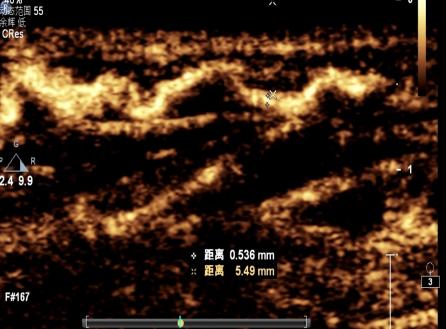

特色技術(shù)超聲醫(yī)學(xué)科設(shè)置有婦產(chǎn)、心臟、血管、腹部、淺表、介入、小兒超聲7個(gè)亞專業(yè)組。診療范圍覆蓋全部臨床超聲檢查和介入治療項(xiàng)目。開展產(chǎn)科三維超聲、經(jīng)食管實(shí)時(shí)三維超聲心動(dòng)圖、心肌應(yīng)變定量分析、淋巴管超聲造影、肌肉骨骼及神經(jīng)超聲、介入超聲治療、各類經(jīng)皮、經(jīng)導(dǎo)管心臟圍手術(shù)期超聲等特殊技術(shù)。

設(shè)備設(shè)施:擁有PHILIPS EPIQ CVx、PHILIPS EPIQ5、PHILIPS CX50、GE Vivid E95、GE Vivid E80、GE Voluson E10、GE LOGIQ E9、HITACHI Preirus等國內(nèi)外先進(jìn)的超聲影像設(shè)備。